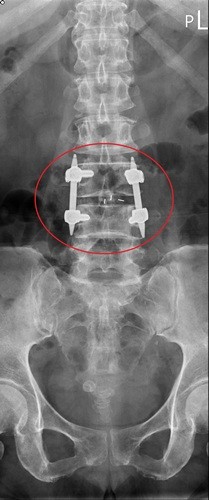

左圖:從影像學檢查發現,高女士的神經壓迫情況很嚴重,細細的神經柱就像被掐住一樣。

右圖:吳聖文醫師透過脊椎微創手術,在特殊工具和高倍率顯微鏡的幫助下,做到神經完全減壓的效果,並儘量保有脊椎本身的骨性結構,最後再透過幾個一公分的小傷口將骨釘置入和固定,達成最後的融合過程。

從影像學檢查發現,高女士的神經壓迫情況很嚴重,細細的神經柱就像被掐住一樣,加上高女士的腎功能差,幾乎只剩下健康人的十分之一左右時,更增加了手術的困難度。吳聖文醫師表示,脊椎微創手術的優點就是傷口小失血量少,不必破壞大量的肌肉和骨頭,在特殊工具和高倍率顯微鏡的幫助下,一樣可以做到神經完全減壓的效果,並儘量保有脊椎本身的骨性結構,最後再透過幾個一公分的小傷口將骨釘置入和固定,達成最後的融合過程。